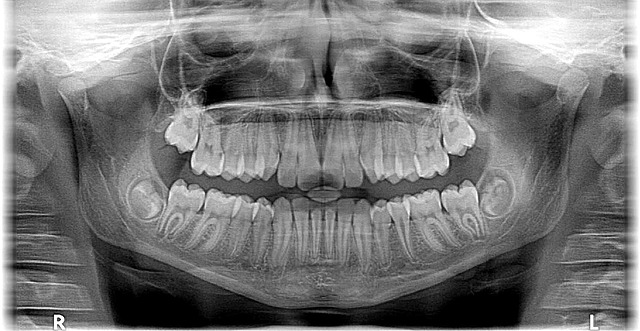

Early detection of bite issues, crowding, or misalignments is crucial. McAllen orthodontists employ advanced diagnostic tools and techniques to identify these problems during developmental stages when interventions are often more effective and less invasive. For instance, interceptive treatments can help create space for erupting teeth, reducing the need for later, more complex procedures like braces. By starting orthodontic care early, patients can enjoy straighter, healthier smiles and avoid the potential social and psychological impacts of dental misalignments.

Additionally, we offer advanced diagnostic tools and technologies to catch potential issues early on. Using modern scanners and intraoral cameras, we can identify subtle changes in your oral structure or signs of decay long before they become painful or noticeable to you. This proactive approach allows us to implement targeted interventions, such as dietary recommendations or customized mouthguards for teeth grinding (bruxism), both of which are common yet often overlooked causes of dental wear and tear. By reaching out to us at 956-686-5000, patients can take advantage of these resources and make informed decisions about their oral health.